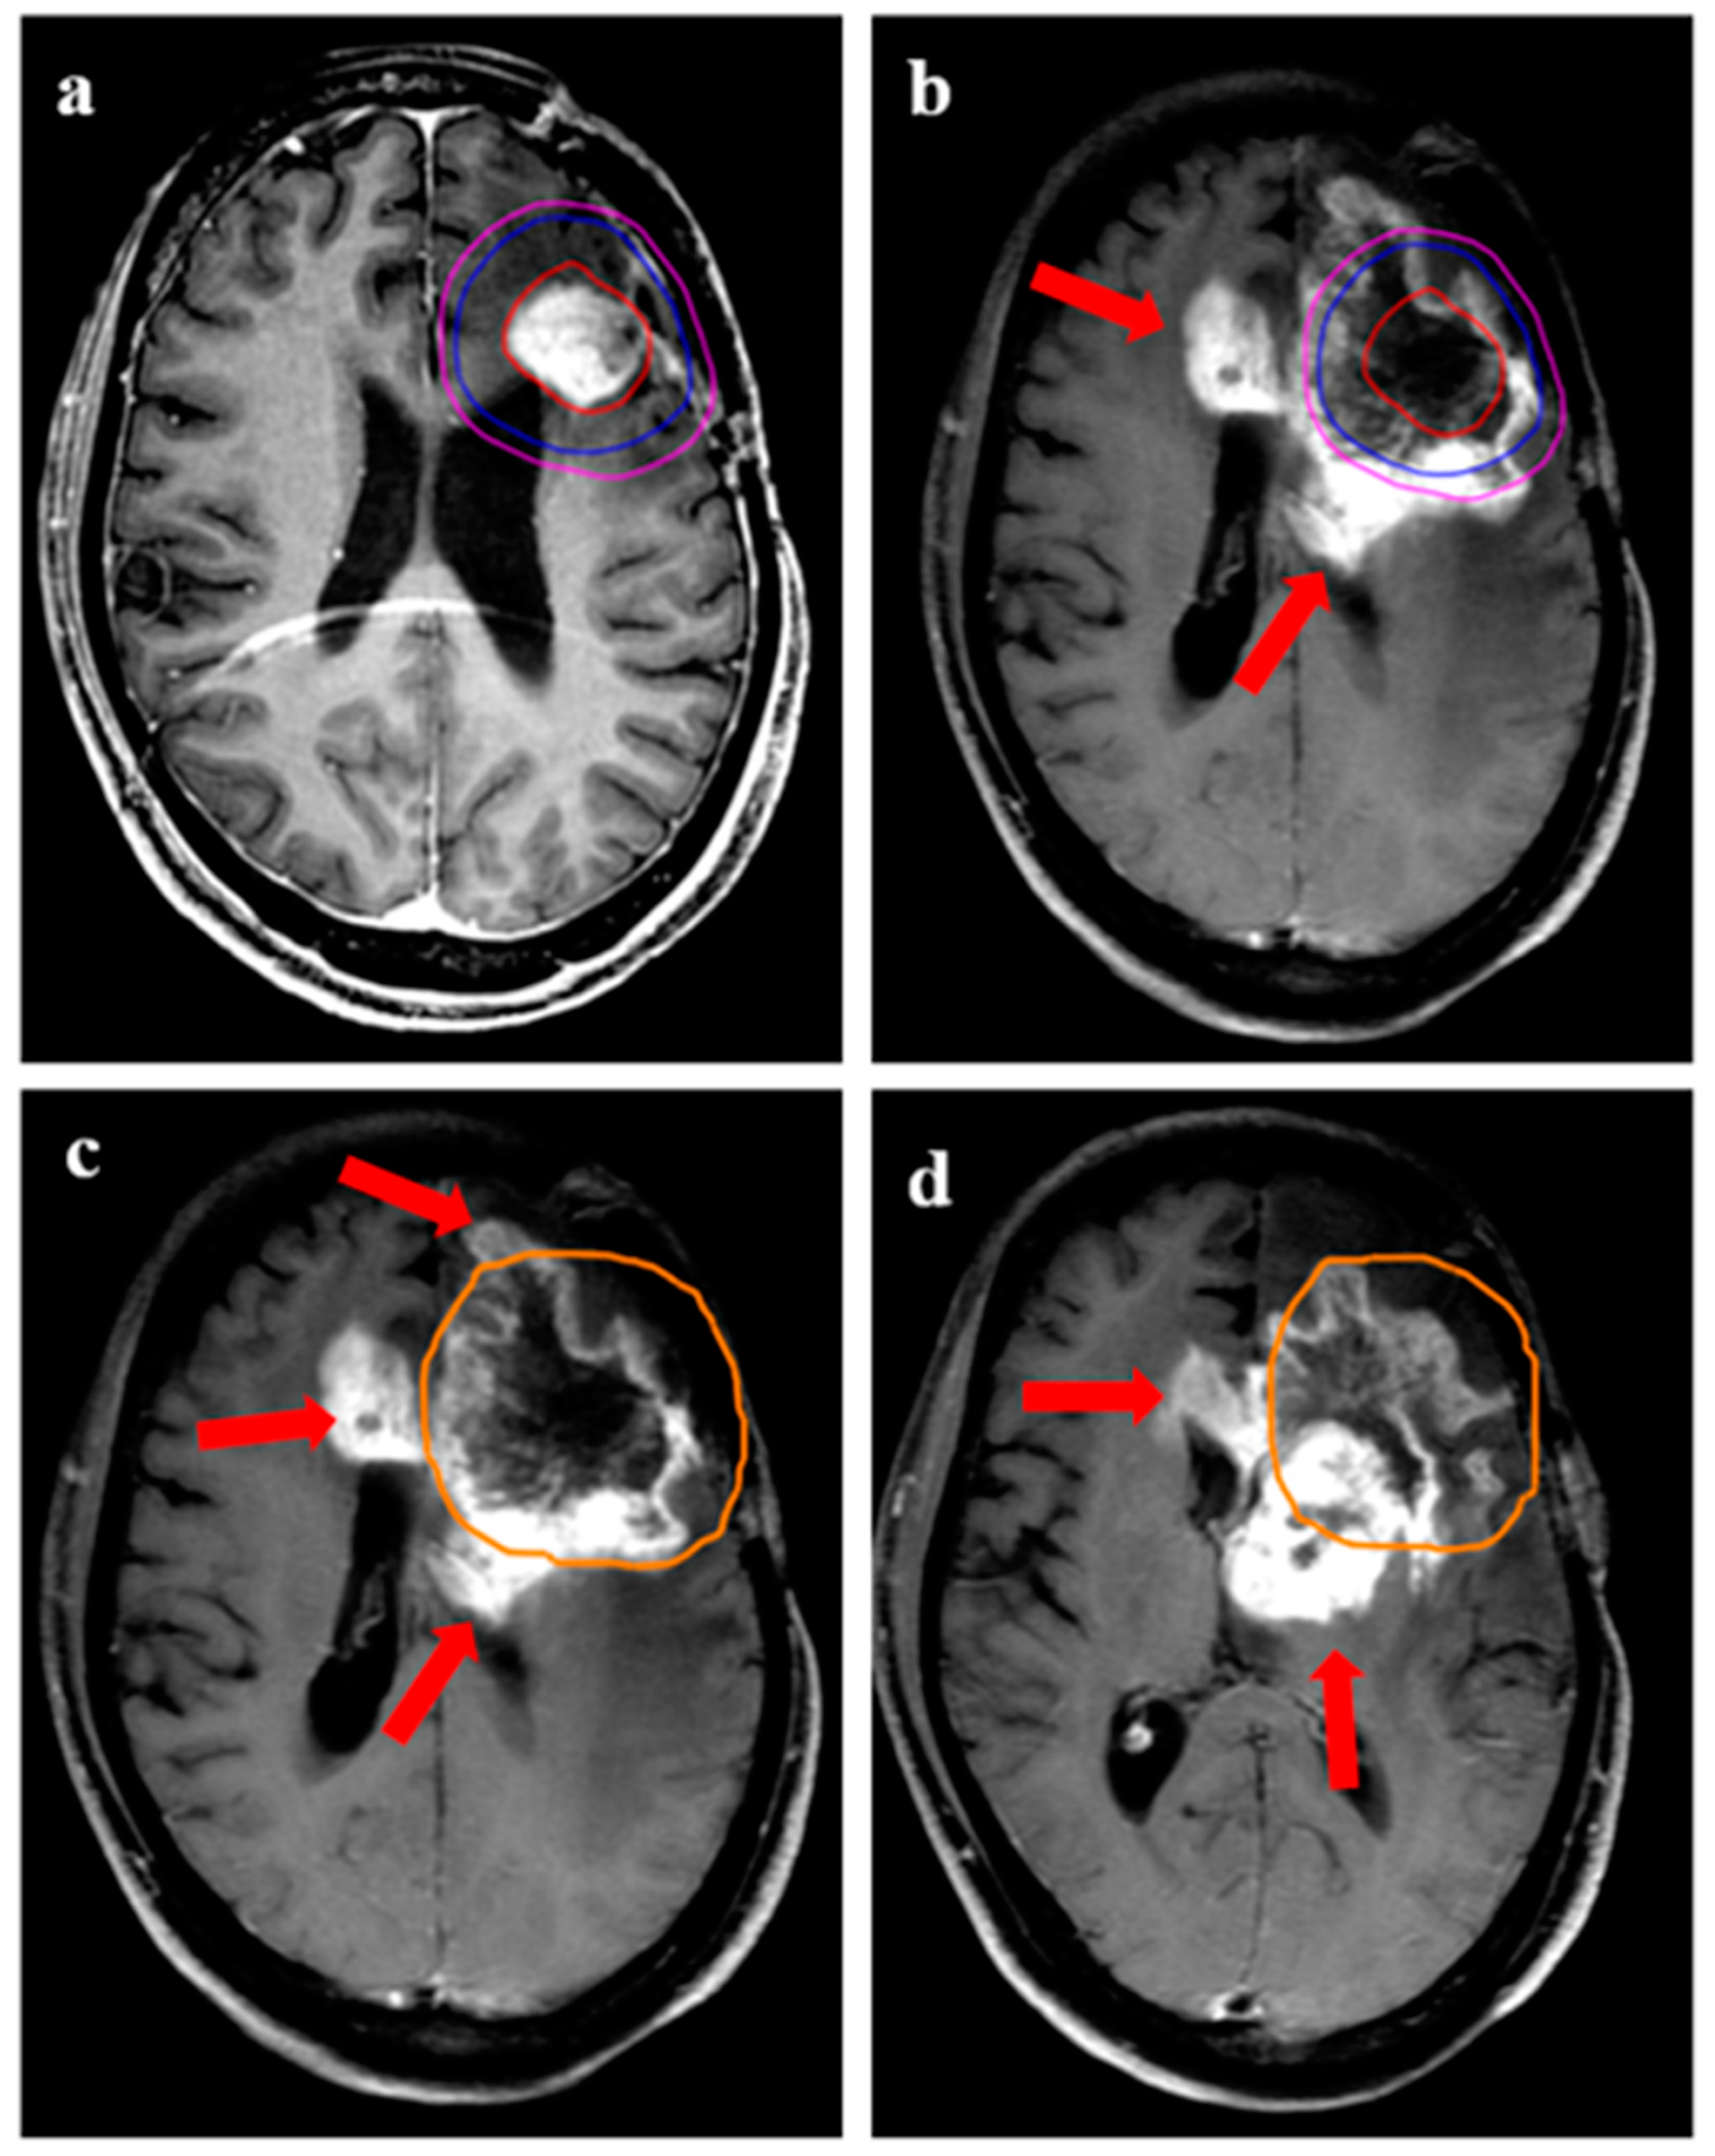

| Patterns of recurrence (with respect to 95% isodose) | |

| Central | 27 (73%) |

| Marginal | 4 (11%) |

| Distant | 6 (16%) |